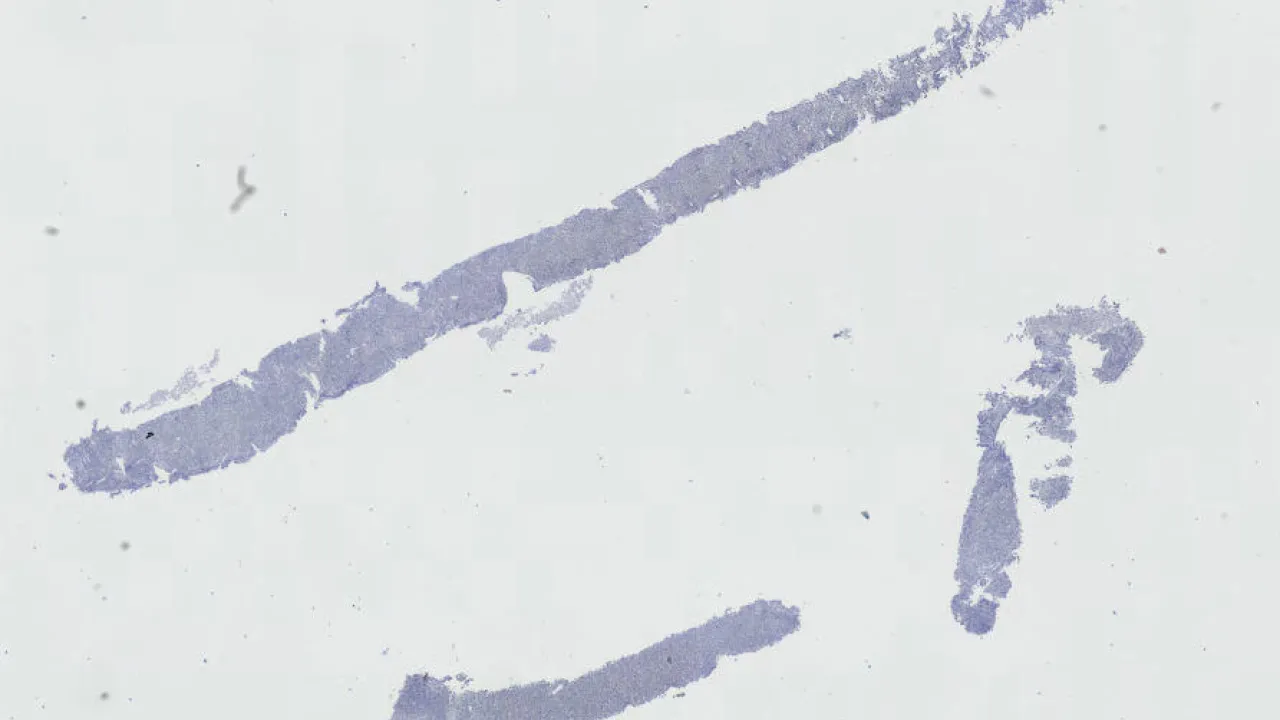

Duodenum, Giardia